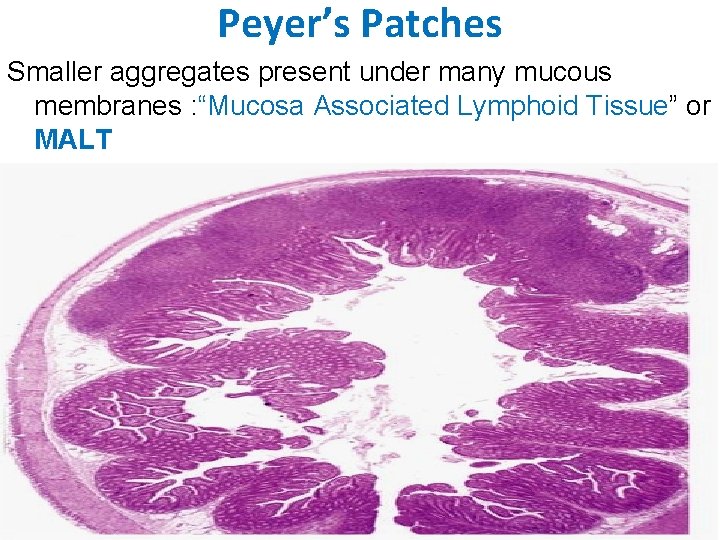

Peyer’s Patches Smaller aggregates present under many mucous membranes : “Mucosa Associated Lymphoid Tissue” or MALT